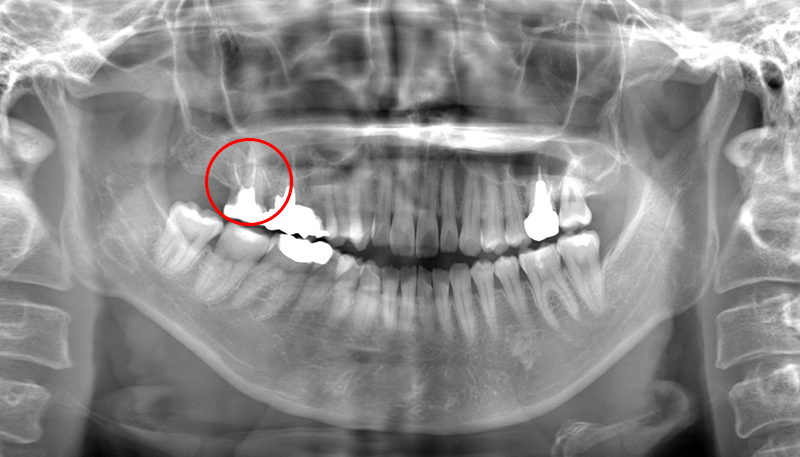

保険治療で撮影可能なパノラマX線写真上では一見病気は無さそうに見えましたが、

CTスキャンを撮影してみると...

実際には大きい根尖病巣(根の先の病気)が見つかりました。CTスキャンで3次元的に見ることで、2次元的なレントゲンでは確認できない病気を発見することができるようになります。

原因発見が難しいケースや難しい根の治療、インプラント、神経との距離が近い親知らずの抜歯などには重要な検査であると考えております。